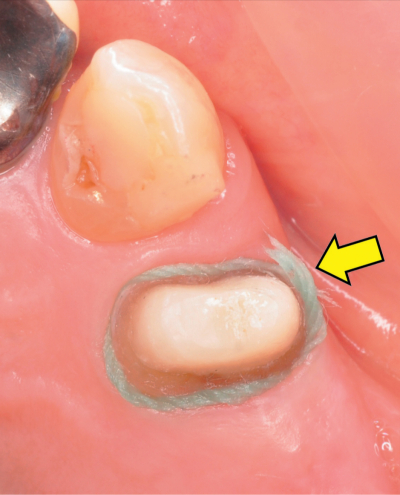

印象採得前の写真を別に示す。矢印で示す材料と併用するのはどれか。1つ選べ。

a. シュウ酸カリウム

b. 塩化ベンゼトニウム

c. フッ化ジアンミン銀

d. 次亜塩素酸ナトリウム

e. 硫酸アルミニウムカリウム